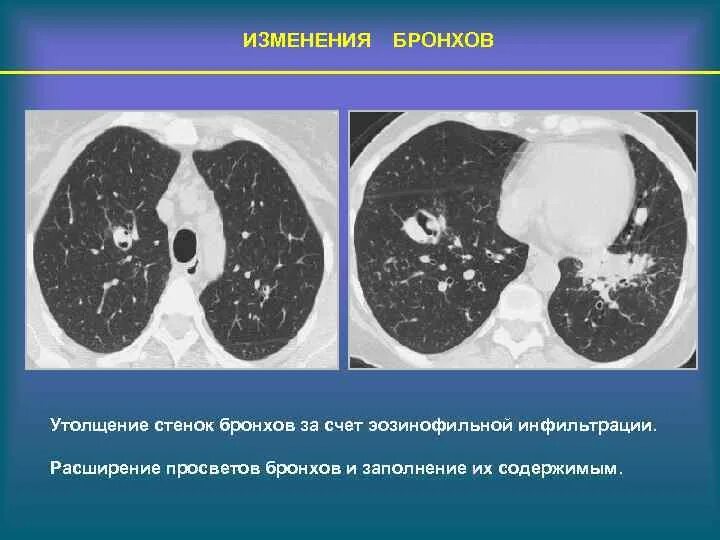

Утолщение бронха